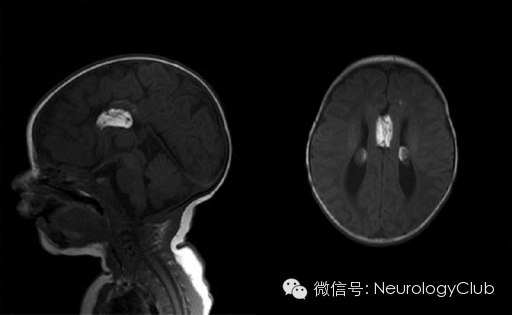

赛车征为胼胝体发育不良(Dysgenesis/Agenesis of the corpus callosum)的典型表现。胼胝体发育不良是胚胎期背部中线结构发育不良所致的胼胝体部分或全部及其周围结构缺如,是最常见的颅脑畸形之一。1899年由Bruce首先描述,1912年由Reil首先报道1例尸检患者,可伴发其他中枢神经系统畸形,也可合并脂肪瘤。一般认为,胼胝体形成顺序为膝部,体部,压部和嘴部,形成越迟的部分发育缺如越常见。

(图示胼胝体脂肪瘤,来自谷歌搜索)